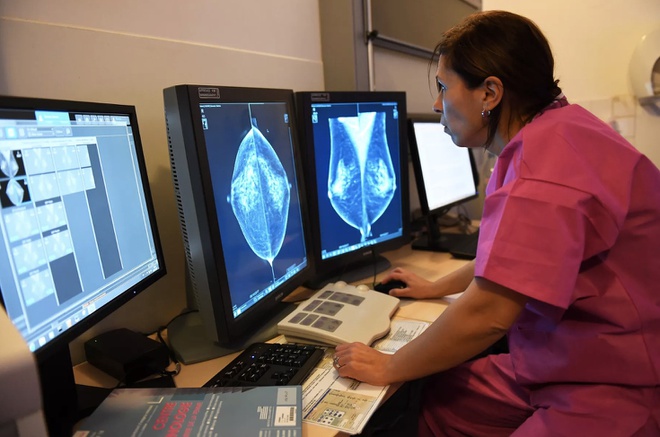

Một bác sĩ đang đọc nhũ ảnh để xác định ung thư. Ảnh: Getty. |

Ung thư vú là bệnh ung thư nguy hiểm thứ hai đối với phụ nữ, chỉ sau ung thư phổi. Phát hiện sớm là cách phòng ngừa tốt nhất và tăng hiệu quả điều trị cho bệnh ung thư vú. Phương pháp chụp X quang bầu ngực, hay còn gọi là nhũ ảnh, là công cụ phát hiện ung thư vú khá hiệu quả nhưng tỷ lệ sai sót vẫn còn cao.

"Nhũ ảnh có hiệu quả cao, nhưng vẫn có vấn đề tồn tại với các kết quả âm tính lẫn dương tính giả", Shravya Shetty, nhà nghiên cứu tại Google và đồng tác giả nghiên cứu nói với The Verge.

Nghiên cứu do Google tài trợ đã sử dụng nhũ ảnh từ 28.000 phụ nữ ở Anh và Mỹ. Trí tuệ nhân tạo quét các hình ảnh X quang, sau đó tìm kiếm các dấu hiệu ung thư vú bằng cách kiểm tra các thay đổi của bầu ngực. Những nhà nghiên cứu sau đó kiểm nghiệm kết quả từ máy tính với các kết luận thực tế của bác sĩ.